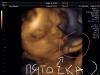

Привет девчонки!))) сходила сегодня на плановое УЗИ ! Моя малышка весит 1900💪🏻😊) слава богу все хорошо! Лежит головкой в низ) но её ножки выпрямлены и она держится ручками за свои пяточки, и лицом трется о пальчики на ножках, и толкает их в рот)))))) даже коленки не сгибает, еле как рассмотрели её личико) еще и пуповинка как шарфик на шее.... в общем гимнастикой там занимается) узистка сказала что если она так лежит, значит ей удобно, но я как всегда переживаю.... Переживалка во мне сидит постоянно(((( в общем у кого так же а????

У меня такой же вес )и лежит головкой вниз)и тоже обвитие)